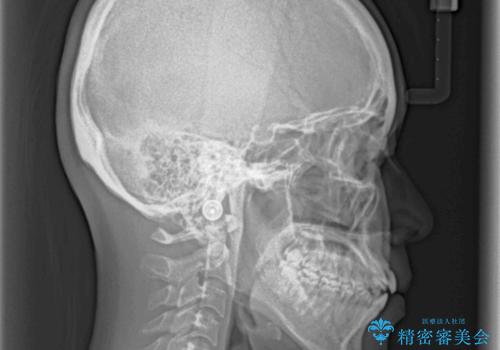

オープンバイトでかみにくい インビザラインによる矯正治療

上下の奥歯を圧下させるようにすることで、前歯を接触させるように計画しました。

上下の隙間に舌が入り込むことがオープンバイトの原因であったため、舌の筋肉のトレーニングも並行して行い、後戻りの抑制を図りました。